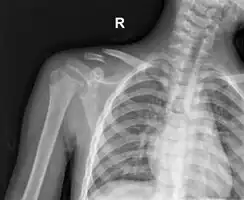

Clavicle fracture